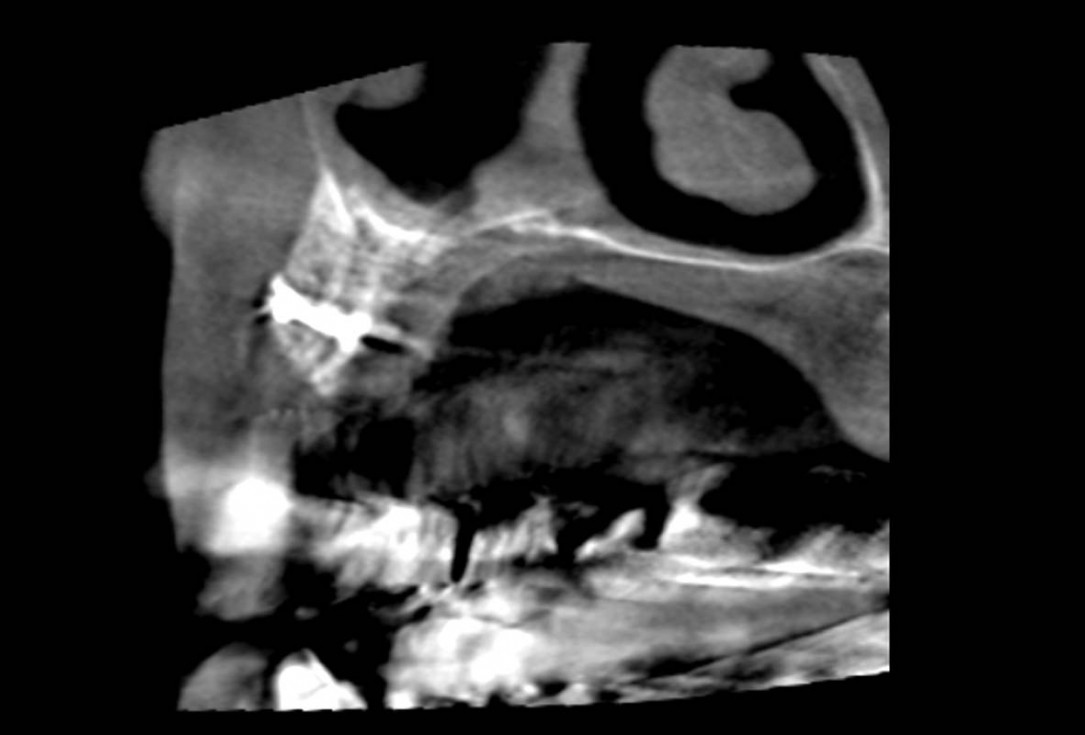

Initial clinical situation: Bone defect in the upper right maxilla (teeth #14-16)